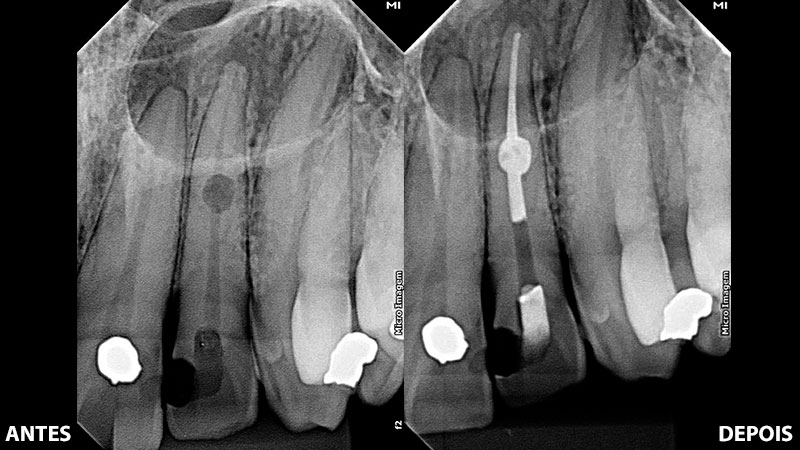

Ao realizar um tratamento endodôntico, é importante que o profissional utilize os melhores recursos afim de se obter uma previsibilidade maior de sucesso, entre eles podemos citar o uso de microscópio operatório, tomografia computadorizada, sistemas para instrumentação rotatórios, reciprocantes e oscilatórios, sistema de captura radiográfica digital, sistema de ultrassom, além do melhores cimentos obturadores com alta capacidade de vedação para impedir futuras infiltrações de microrganismos na cavidade do dente. No caso clínico apresentado nas imagens acima, realizado pelo Dr. Fabiano Bonatto, foram utilizados todos os recursos citados acima.

O cimento biocerâmico possui capacidade de estimular a regeneração tecidual da região afetada, além de proporcionar uma excelente vedação hermética e a formação de ligação química com a dentina. Além disso, quando comparado aos cimentos tradicionais, o biocerâmico se destaca por suas propriedades antibacterianas através do elevado ph, que são fundamentais para o êxito do tratamento endodôntico.